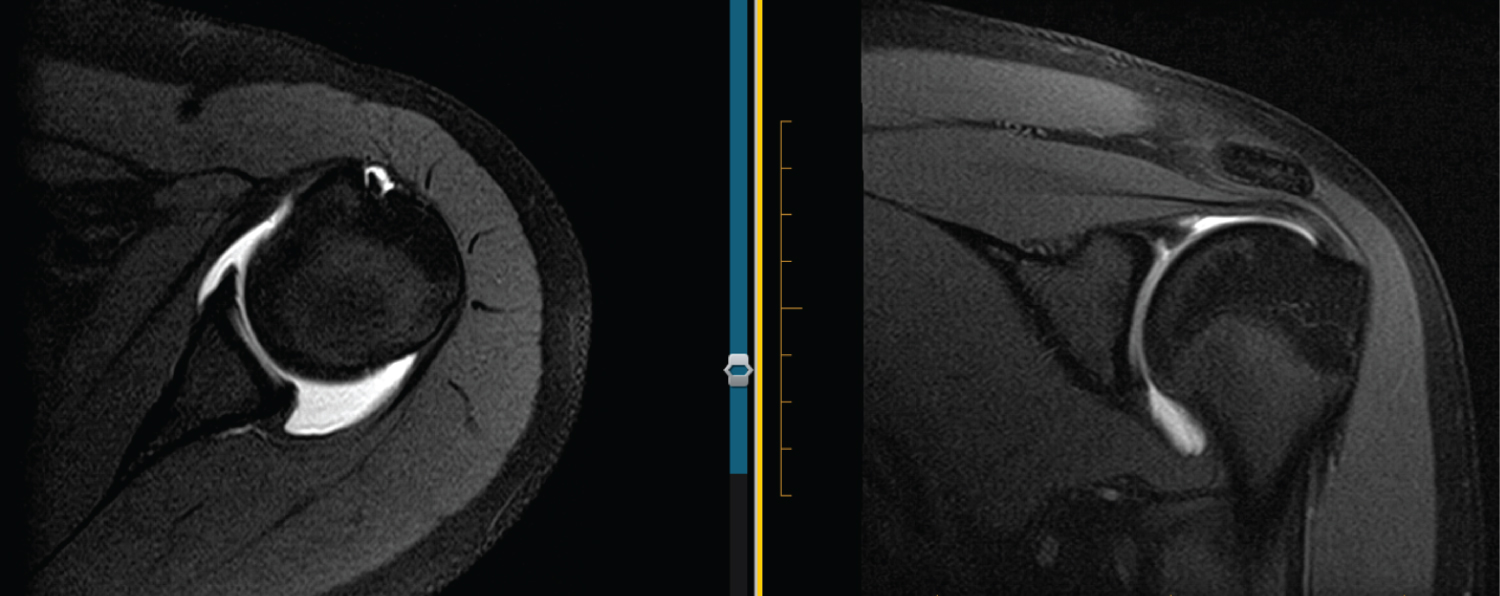

Figure 4: 16 M R MRA. Axial view shows blunted, rounded labrum. ABER view shows intact IGHL and labrum (normal). View Figure 4

Figure 5: 17 F L MRA. Axial view shows blunted, rounded labrum. ABER view might have some undercutting of labrum, otherwise no tear of IGHL or labrum appreciated. View Figure 5